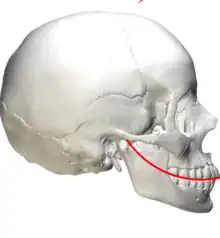

In anatomy, the Curve of Spee (also called von Spee's curve or Spee's curvature) is defined as the curvature of the mandibular occlusal plane beginning at the canine and following the buccal cusps of the posterior teeth, continuing to the terminal molar. According to another definition the curve of Spee is an anatomic curvature of the occlusal alignment of the teeth, beginning at the tip of the lower incisor, following the buccal cusps of the natural premolars, and molars and continuing to the anterior border of the ramus. It is named for the German embryologist Ferdinand Graf von Spee (1855–1937), who was first to describe the anatomic relations of human teeth in the sagittal plane.

The pull of the main muscle of mastication, the masseter, is at a perpendicular angle with the curve of Spee to adapt for favorable loading of force on the teeth. The long axis of each lower tooth is aligned nearly parallel to their individual arch of closure. The Curve of Spee is, essentially, a series of sloped contact points. It is of importance to orthodontists as it may contribute to an increased overbite. A flat or mild curve of Spee was essential to an ideal occlusion.[1]

The Curve of Spee is basically a part of a circle (8-inch diameter) which has its circumference as the anterior ramus of mandible. Ideally, it is aligned so that a continuation of this arc would extend through the condyles. The curvature of this arc would relate, on average, to part of a circle with a 4-inch radius. It is the only Anteroposterior curve of occlusion.